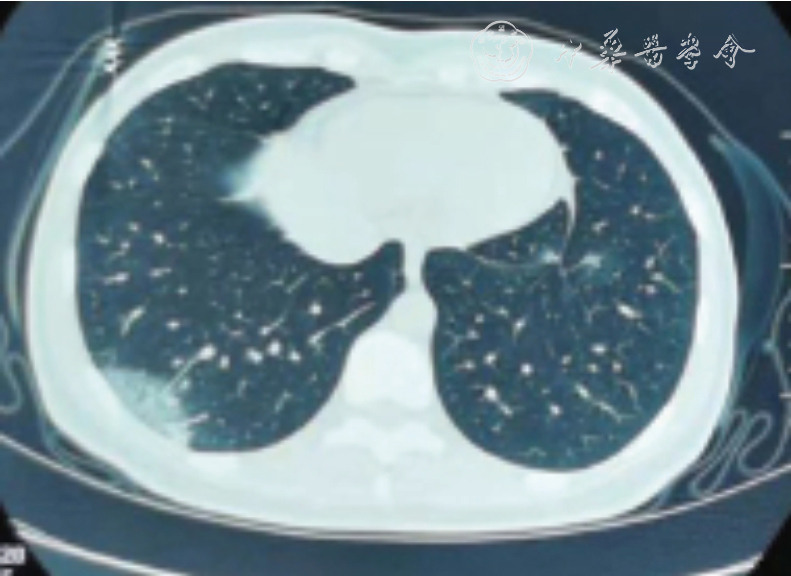

图3 重症新型冠状病毒肺炎患者胸部影像 注:肺部影响可见多叶段受累,间质性肺炎,磨玻璃样,实变影